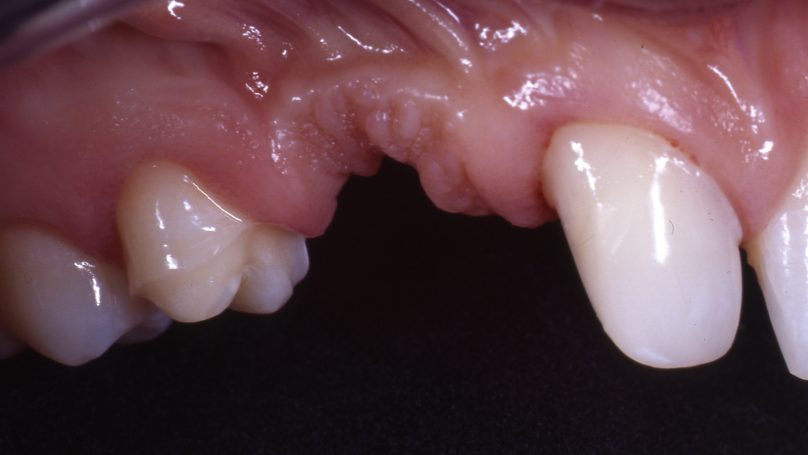

Teleskopierende Oberkieferbrücke mit Vorher- und Nachher-Situation des Patienten.

Teleskopierende Oberkieferbrücke. Wie die eigenen Zähne, aber einfach zu reinigen.